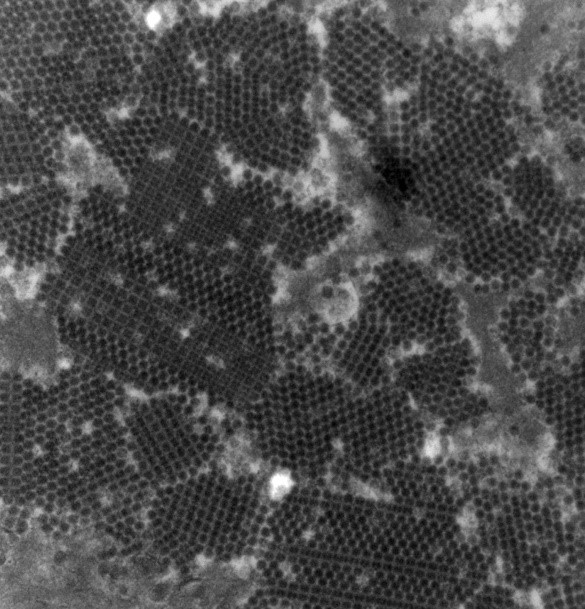

(移植腎ポリオーマウイルス腎症のウイルス粒子×40,000)